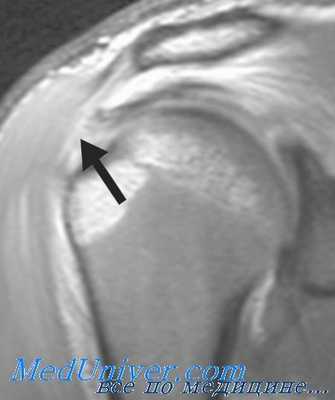

В сомнительных случаях пациента направляют на МРТ плечевого сустава. При тендините на МРТ определяется утолщение оболочек сухожилий и капсулы сустава, при травматическом повреждении виден участок разрыва. Для исключения других заболеваний и патологических состояний (артроза, последствий перелома или вывиха) назначают рентгенографию плечевого сустава. При отсутствии кальцификации рентгенологическая картина в пределах нормы. При кальцифицирующем тендовагините на снимках видны участки обызвествления.